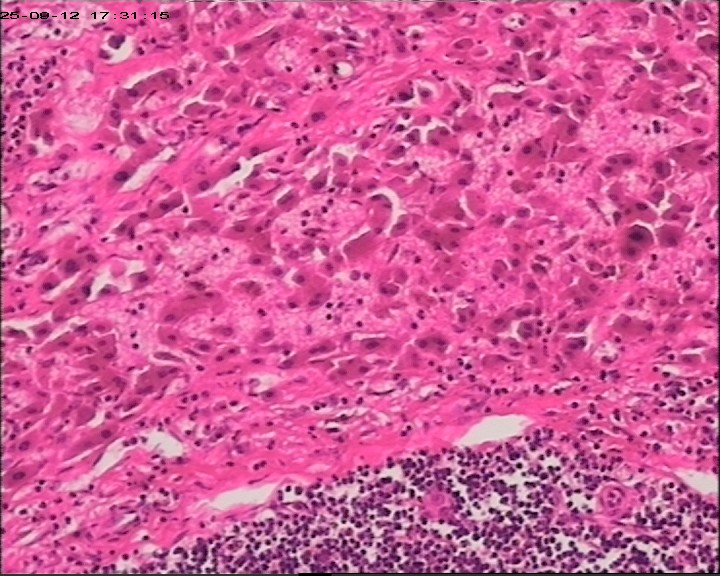

性别年龄47岁临床诊断肝占位性质待查,肝棘球蚴病?

大体所见肝组织一块,大小为20*18*15cm,切面多房囊性,部分内含坏死样物。

建议:描述性病理诊断!(感觉符合棘球蚴病病理改变,但未见明显的直接证据!)

大体检查有没有看到粉皮样的角质膜?取角质膜在镜下找到头节有助于诊断。